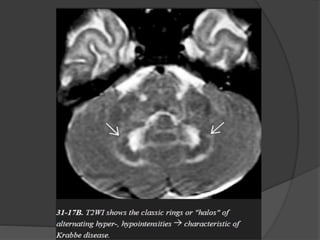

Globoid Cell Leukodystrophy (Krabbe Disease)

GLD is characterized by the presence of unique "globoid" cells in the demyelinating

lesions.

Imaging

NECT scans :

Bilaterally symmetric calcifications

in the thalami, basal ganglia,

internal capsule, corticospinal

tracts, and dentate nuclei of the

cerebellum can sometimes be

Identified.

Classic MR findings in GLD are corticospinal tract hyperintensity on T2/FLAIR

with confluent symmetric demyelination in the deep periventricular WM.

The subcortical U-fibers are typically spared. Bithalamic hypointensity on

T2WI is common.

Diffusion tensor imaging (DTI) may demonstrate reduced fractional anisotropy

in the corticospinal tracts before other abnormalities appear.

MRS findings of elevated choline and decreased NAA in the hemispheric WM

are characteristic but nonspecific.

Cerebellar findings appear early in the disease course.

Alternating "halo" or ring-like hypointensities on T1WI and hyperintensities

on T2WI can be identified in the cerebellar WM surrounding the dentate

nuclei.

Another distinctive feature of GLD is enlargement of the intracranial optic

nerves and chiasm. Diffusely enlarged, enhancing cranial nerves and cauda

equina nerve roots have also been reported in GLD.

Differential Diagnosis

The WM changes in metachromatic leukodystrophy and vanishing white

matter disease may initially appear quite similar, but these disorders lack

the basal ganglia/thalamic calcifications typical of GLD.